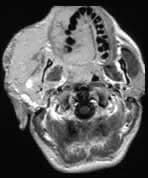

There is an enormous facial angioma extending through the palate to almost obliterate the oro-pharyngeal airway. A small extension into the middle cranial fossa from the infra temporal fossa is shown. Signal change is present in the immediately overlying brain suggesting a breach in the dura. Bone is partly destroyed in and around the right orbit, especially the right frontal bone.